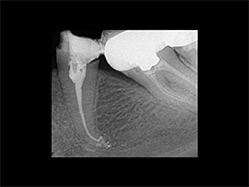

Slika 6:Vitalni prvi gornji molar sa ireverzibilnim pulpitisom. Uočljiv je izrazito dugačak palatinalni kanal (oko 31mm),koji je ipak zapečaćen zajedno sa petljom lateralnog kanalom zahvaljujući dobroj hemijskoj obradi kanala koja je omogućila kompaktnost punjenja.